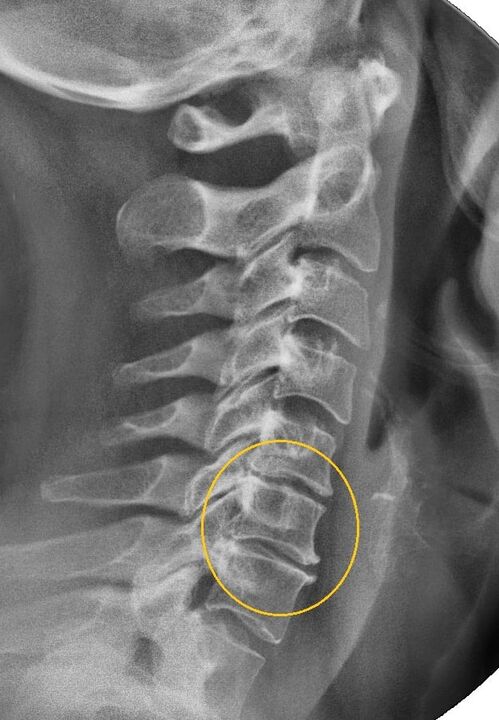

The most informative diagnostic procedure is radiography.1st degree pathologies correspond to the 1st or 2nd radiological stage.The resulting images visualize typical signs of the disease.

| Radiographic stages of 1st degree cervical osteochondrosis | Characteristic signs |

|---|---|

| Stage 1 | Small changes in the curvature of the spine in the cervical region, affecting one or more segments |

| Stage 2 | Slight thickening of the intervertebral discs, deformation of the uncinate processes, straightening of the lordosis, small growths of the bony structures |